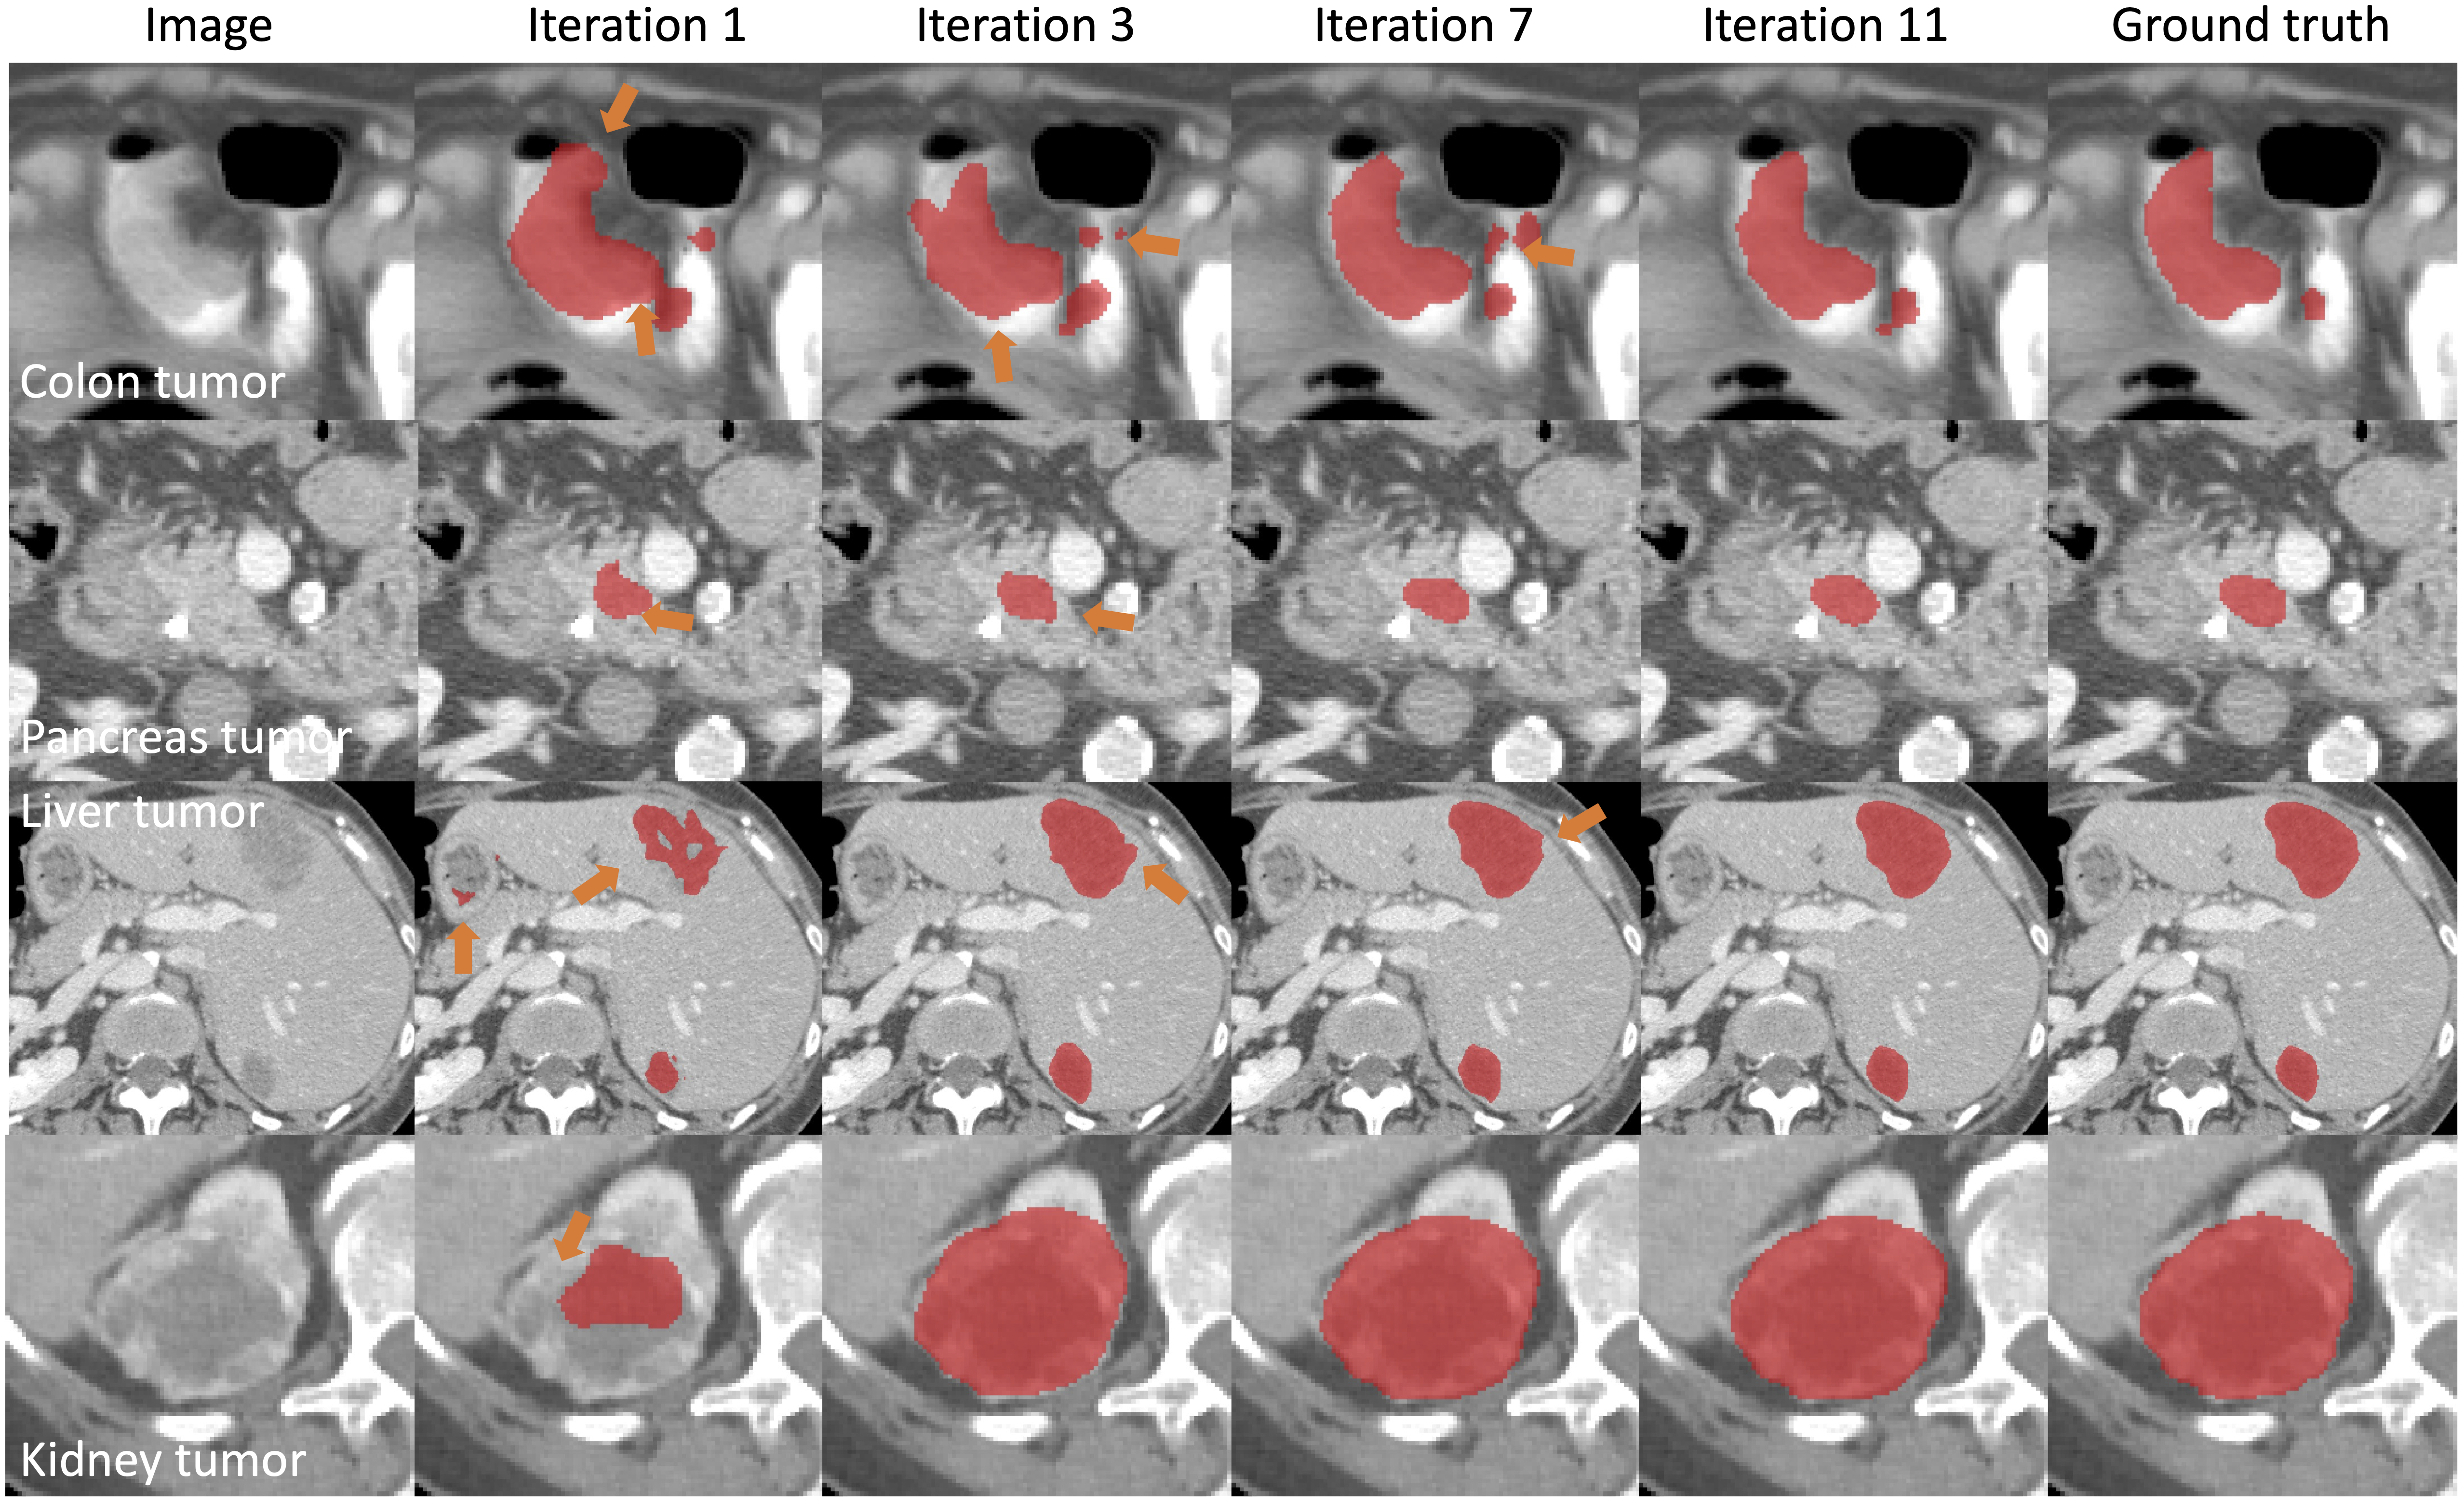

PRISM tumor segmentation examples

Briefly, PRISM produces tumor segmentation with mean Dice values of 93.79 (colon), 94.48 (pancreas), 94.18 (liver), and 96.58 (kidney).

| Iterative correction for colon tumor |  |

| Iterative correction for multiple tumors |  |